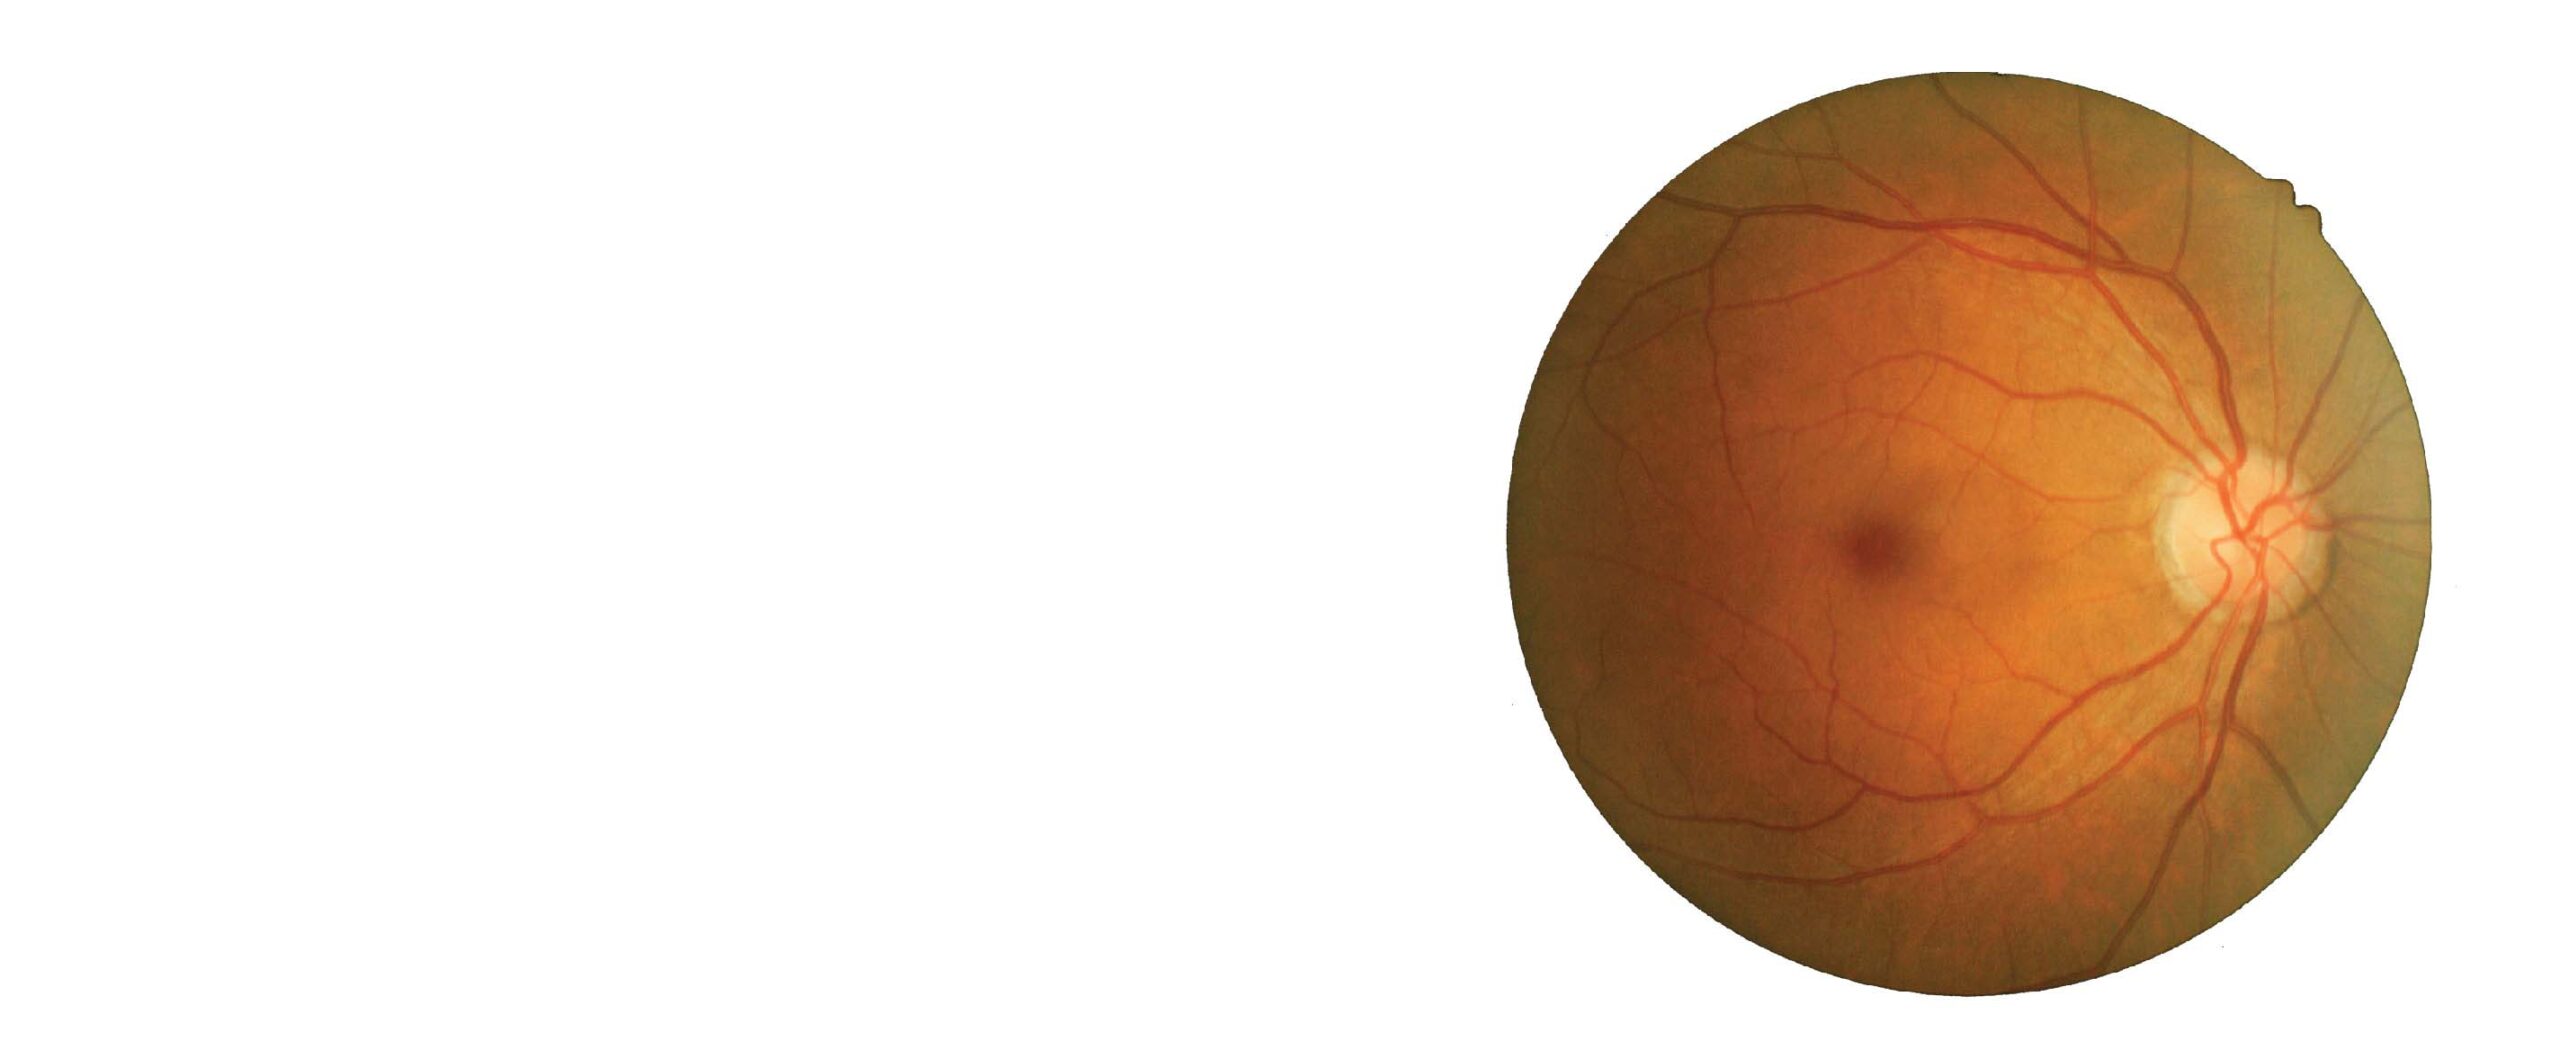

BRVO stands for Branch Retinal Vein Occlusion, a condition that occurs when one of the small veins in the retina becomes blocked or impeded, leading to vision loss. It is a common retinal vascular disorder that can cause blurred or distorted vision, visual field loss, and other visual impairments. BRVO is usually associated with ageing and underlying health conditions such as hypertension, diabetes, and atherosclerosis. Ayurvedic treatment for BRVO includes a combination of herbal medications, dietary modifications, and lifestyle changes to manage symptoms and promote overall health. It aims to address the underlying imbalances in the body and prevent irreversible vision loss.

BRVO (Branch Retinal Vein Occlusion) occurs when one of the small veins in the retina becomes blocked or occluded, leading to vision loss. The exact cause of BRVO is not always clear. Still, it is commonly associated with underlying health conditions such as hypertension, diabetes, atherosclerosis, and other cardiovascular diseases that affect the blood vessels. In addition, age-related changes to the blood vessels in the retina might also contribute to the development of BRVO. Other risk factors that can increase the likelihood of developing BRVO include smoking, high cholesterol, obesity, and a sedentary lifestyle. Therefore, it is vital to identify and manage these risk factors to prevent or minimize the occurrence of BRVO. Ayurvedic BRVO eye treatment can help with this condition holistically by addressing the root cause.